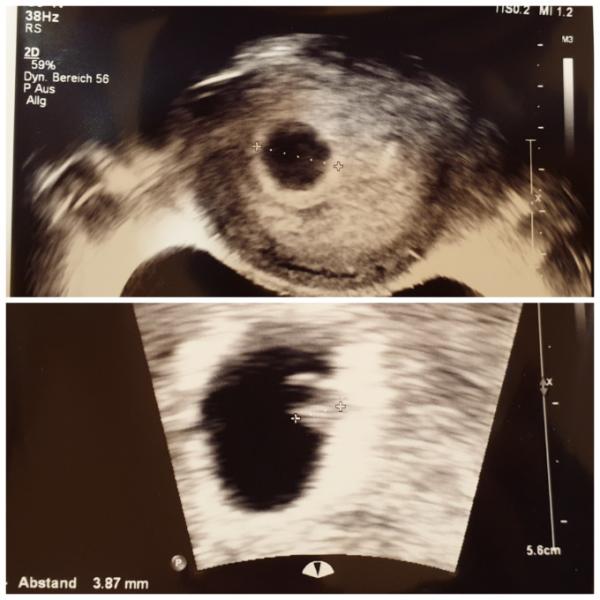

Guten Abend ihr Lieben, Auch ich durfte heute zum 1. Ultraschall bei 6+0 und ich habe eine Fruchthöhle mit Dottersack und Embryo mit Herzschlag gesehen Bin heulend vom Stuhl gesprungen vor Freude Jetzt muss alles noch so schön bleiben und dann gibt es im Januar ein lang ersehntes Geschwisterchen

Bild zu 1. FA Termin :) - Forum für Januar - Mamis